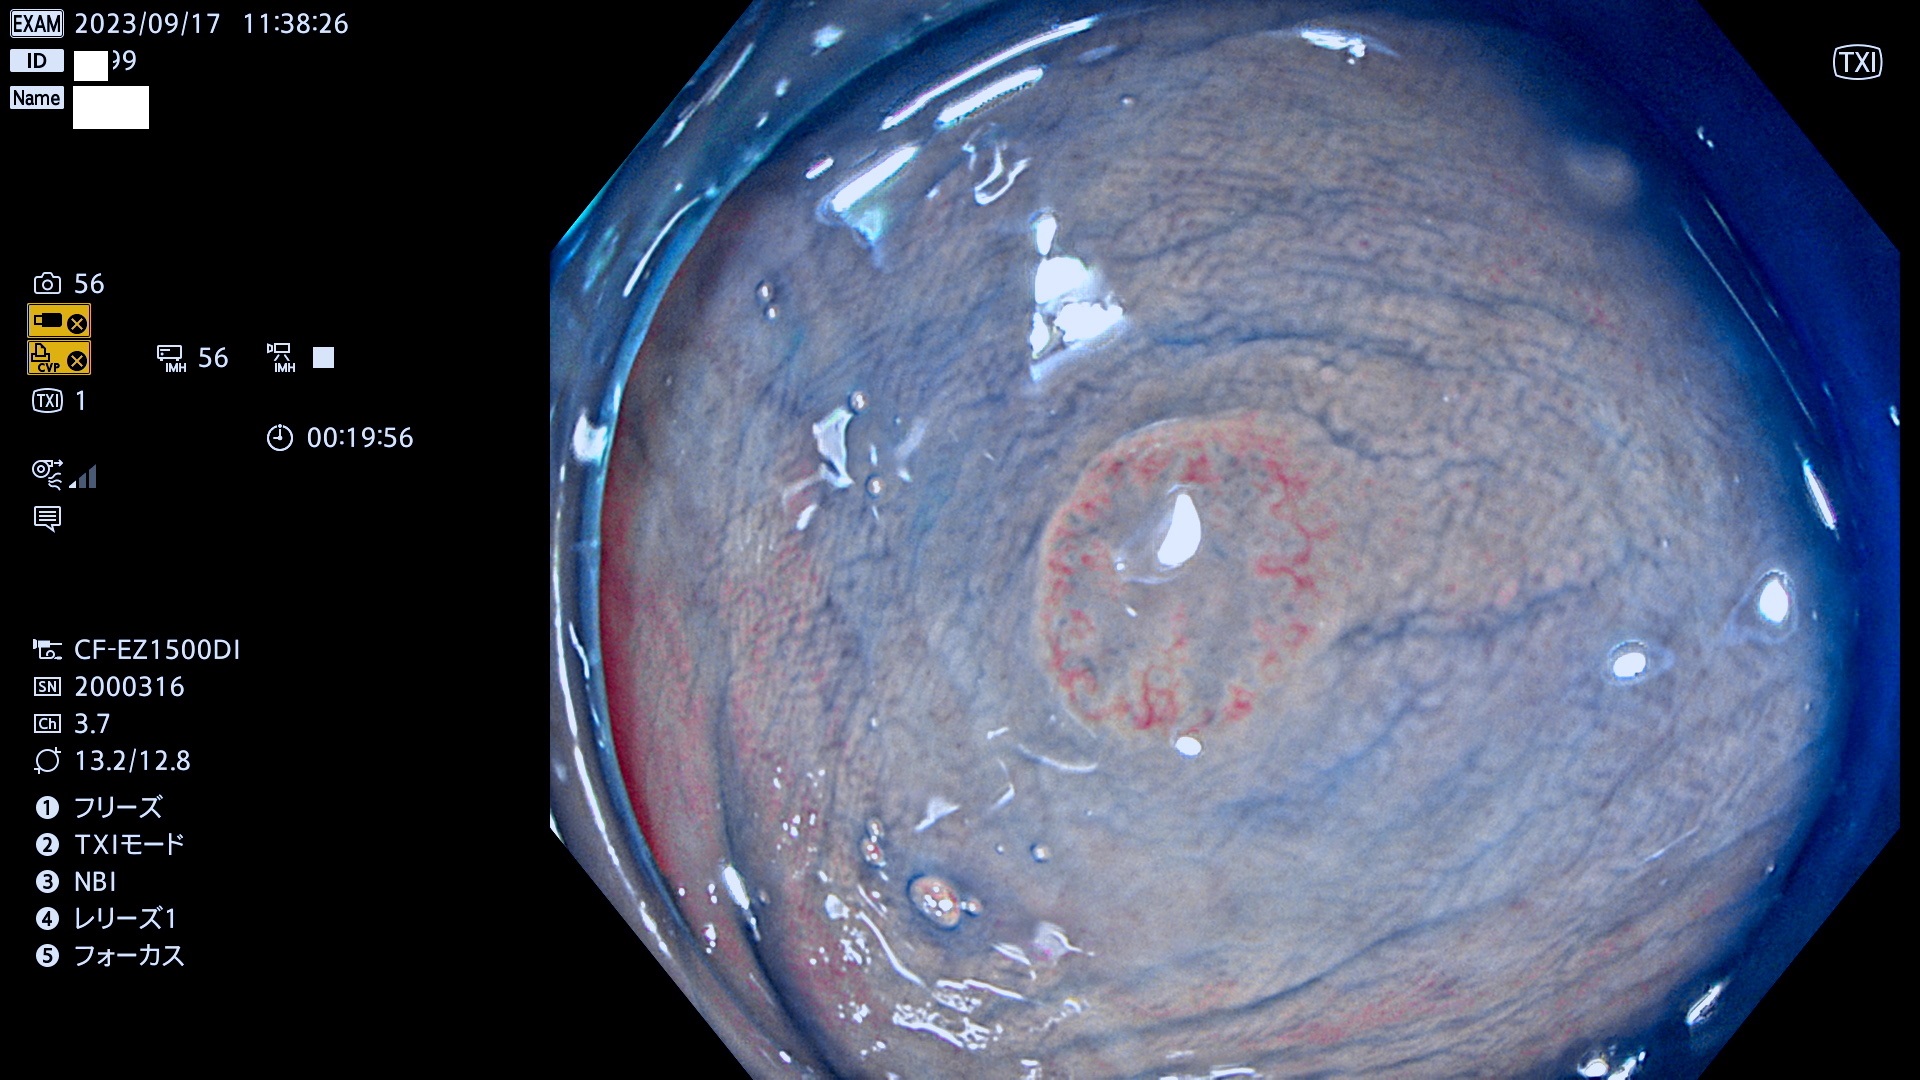

今週のUb、Uc型腺腫

表面型腺腫(Flat Adenoma)の中で、完全に平坦な物をUb、陥凹している物をUcと呼びます。平坦隆起型(Ua)よりも、発見が難しく危険な病変です。このタイプは「内視鏡後・大腸癌の重要犯人」であり、この発見率は「腺腫発見率」よりも、重要な意味があります。

毎週の検査(木・金・土・日)に発見されたUb、Uc型・腺腫を、その週の日曜の夜にUPし1週間、提示します。

抽出の対象期間 2023年9月14日(木)〜9月17(日)の4日間(48件の検査)7件